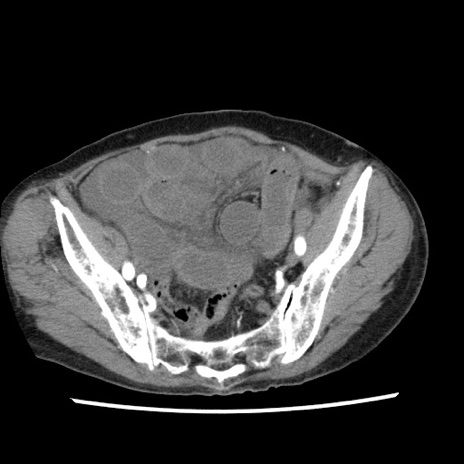

冠状断像

【症例】80歳代女性

【主訴】腹痛

【現病歴】8時間前から腹痛あり来院。

【既往歴】糖尿病、脂質異常症、子宮体癌にて子宮全摘術

【身体所見】意識清明・会話良好だが腹痛で苦悶様、全腹部にわたって反跳痛と圧痛あり

【データ】WBC 13600、CRP 0.14、LDH 224、CK 90